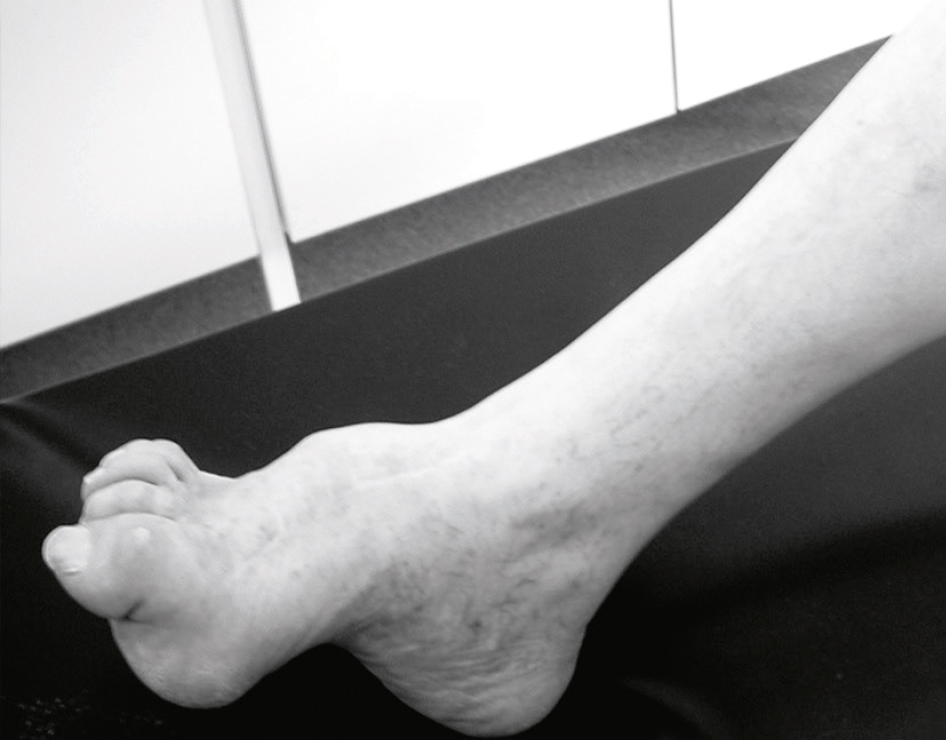

b Symptômes et signes moteurs

• • Déficit des muscles de la loge antérolatérale de jambe (fibulaire, tibial antérieur, long extenseur des orteils, long extenseur de l’hallux, court extenseur des orteils).

• • L’ensemble réalise un steppage lors de la marche.

c 118Causes

• • Compression externe aiguë indolore : paralysie posturale :

•

• – appui prolongé sur la région de la tête de la fibula;

• – position assise jambes croisées;

• – position allongée et amaigrissement (séjour en réanimation);

• – travail en position agenouillée.

• • Vascularite : paralysie aiguë douloureuse.

d Traitement

• • Abstention en cas d’atteinte posturale aiguë.

• • Chirurgie en cas de formes progressives ou si une cause locale de compression a été trouvée (kyste synovial articulaire de la fosse poplitée).